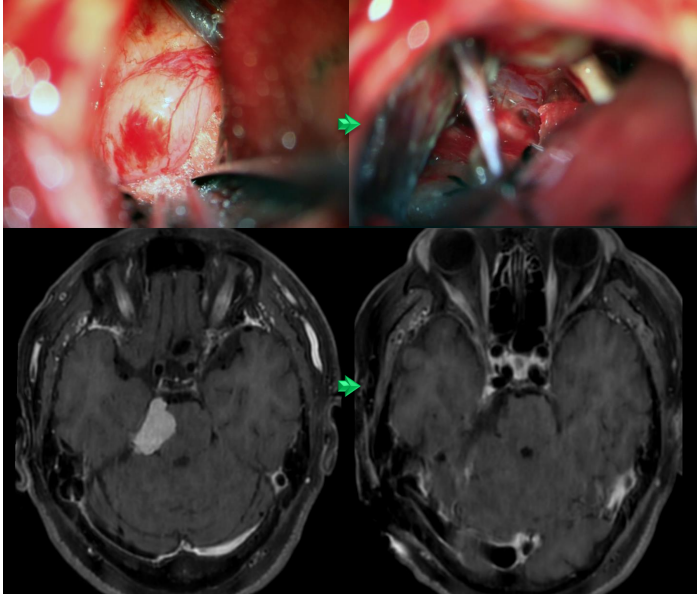

下の写真の症例は、認知症のような症状で発症しました。

- 治療が必要な髄膜腫の標準治療: 手術摘出。病理検査で放射治療の追加の有無を検討する

- 上記治療内容: 手術摘出。病理検査でatypical meningiomaと診断。放射線治療を追加

- 費用:約1週間の入院で自己負担額は、1割負担 約10万円(当院での治療は手術のみ、放射線治療費は別途必要)

- リスク・合併症:出血、感染、脳梗塞、神経障害、疼痛、その他